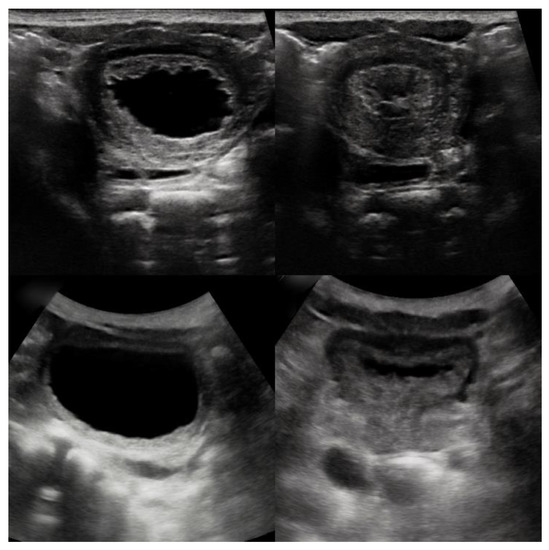

2. Case Presentation

2.1. Case 1

2.2. Case 2